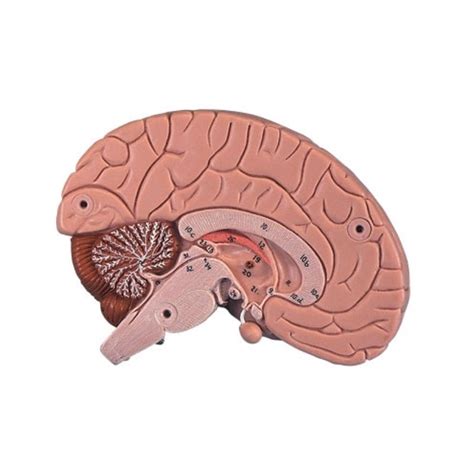

Najnovšie výskumy naznačujú, že intenzívne pohyby dieťaťa v treťom trimestri majú špecifický význam. Podľa štúdie zverejnenej v časopise Scientific Reports si dieťa týmito pohybmi vytvára mapu vlastného tela pre svoj mozog. Náraz na stenu maternice slúži ako spätná väzba, ktorá formuje mozog. U predčasne narodených detí je preto dôležité, aby mali v inkubátore povrch, ktorý pri pohybe ucítia, aby sa podpora ich vývoja mohla realizovať.

Tieto spontánne pohyby a spätná väzba z prostredia sú nevyhnutné pre správne fungovanie mozgu, a to nielen u ľudí, ale aj u zvierat. Pohyby končatín v maternici pomáhajú rozvíjať zmyslové vnemové schopnosti.

Okrem vývoja mozgu majú pohyby bábätka v brušku aj ďalší dôležitý význam. Pomáhajú tvarovať svaly, kosti a kĺby dieťaťa. Je to akýsi tréning pred narodením, ktorý pripravuje dieťa na život mimo maternice.

Pohyby bábätka môžeme vnímať aj ako formu "kalibrácie" pred pôrodom. Dieťa si nastavuje svoj mozog na budúce skúsenosti, pohybové aktivity, reakcie tela a celkový vývoj. Tento proces je dôležitý aj po narodení, keď pohyby končatín naďalej súvisia s rozvojom mozgových funkcií až do školského veku.